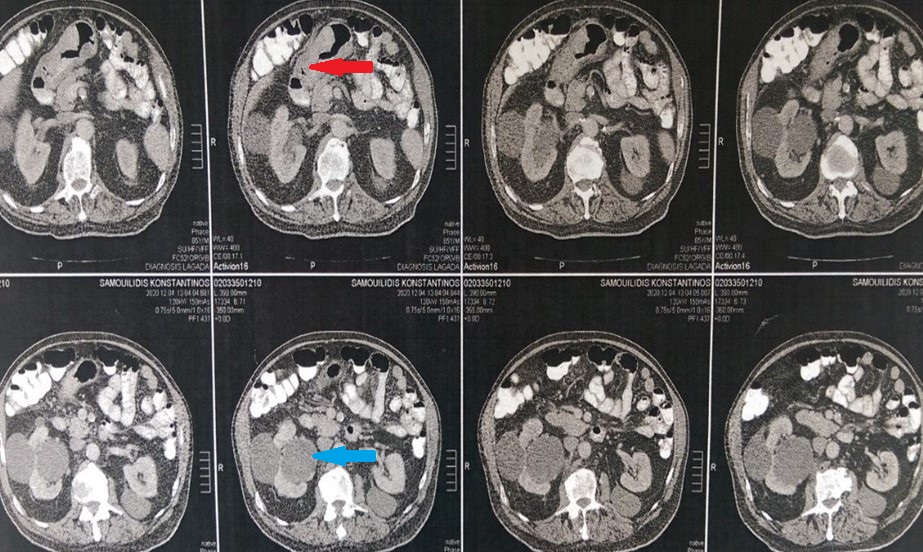

CT Scan. The gastric tumors are obvious (red arrow). Incidental finding right sided sizable renal cysts (blue arrow)